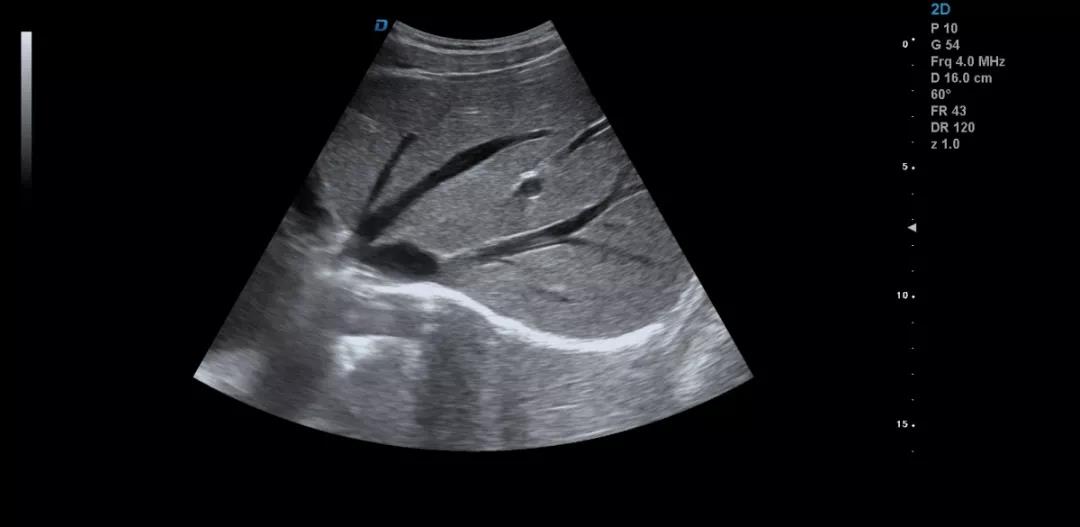

眾所周知,肝臟有很多檢查死角,成為超聲檢查的盲區(qū),如肺和骨所掩蓋處,肝右前上段及右后上段的膈頂部,左外葉外側(cè)角區(qū),沿肝臟表面的肋骨下區(qū)等等部位,只有極其細(xì)致的檢查配上精巧的手法才能盡可能的顯示清楚這些部位。

如果我們能夠細(xì)致的檢查每個(gè)病人,所謂的肝臟死角能夠盡可能的探測(cè)到,肝臟的死角其實(shí)只有膈頂部,其他的部位如果能細(xì)致檢查都可以探測(cè)到。

肝臟膈頂部掃查體會(huì):

1)一般是讓患者深吸氣,讓肝臟下移,然后探頭盡量上翹;

2)當(dāng)然很多患者因肥胖或肺氣的干擾會(huì)顯示更差,這時(shí)我就讓患者深呼氣,把氣全部吐干凈,然后屏氣掃查;

3)還有就是不要沿著肋間隙掃查,而是和肋間隙成一定的角度緩慢向右上方腋前線(xiàn)掃查;

4)在平臥位掃查時(shí),在橫切腎臟時(shí)探頭盡量上翹,甚至與腹壁平行,當(dāng)然在右側(cè)肋緣下也行;

5)變換體位掃查,肝臟因重力作用產(chǎn)生移位。左側(cè)臥位、右側(cè)臥位、各種斜位、還有站立位等等。

掃查肝臟時(shí)要配合患者的呼吸運(yùn)動(dòng),采取你動(dòng)我靜,你靜我動(dòng)的掃查方法,并最大限度的側(cè)動(dòng)探頭,最大角度的顯示肝臟。

發(fā)現(xiàn)肝臟病變時(shí)要多切面多角度掃查,可以了解病變的解剖位置并排除假陽(yáng)性。